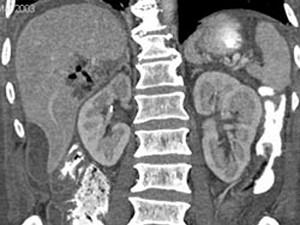

问题 男,44岁,发热、右上腹痛、压痛,右下肺呼吸音低,影像检查如图,最佳诊断是 ( )

选项 A.腹腔积液 B.膈下脓肿 C.肝包膜下出血 D.肝硬化腹水 E.肝癌

答案 B